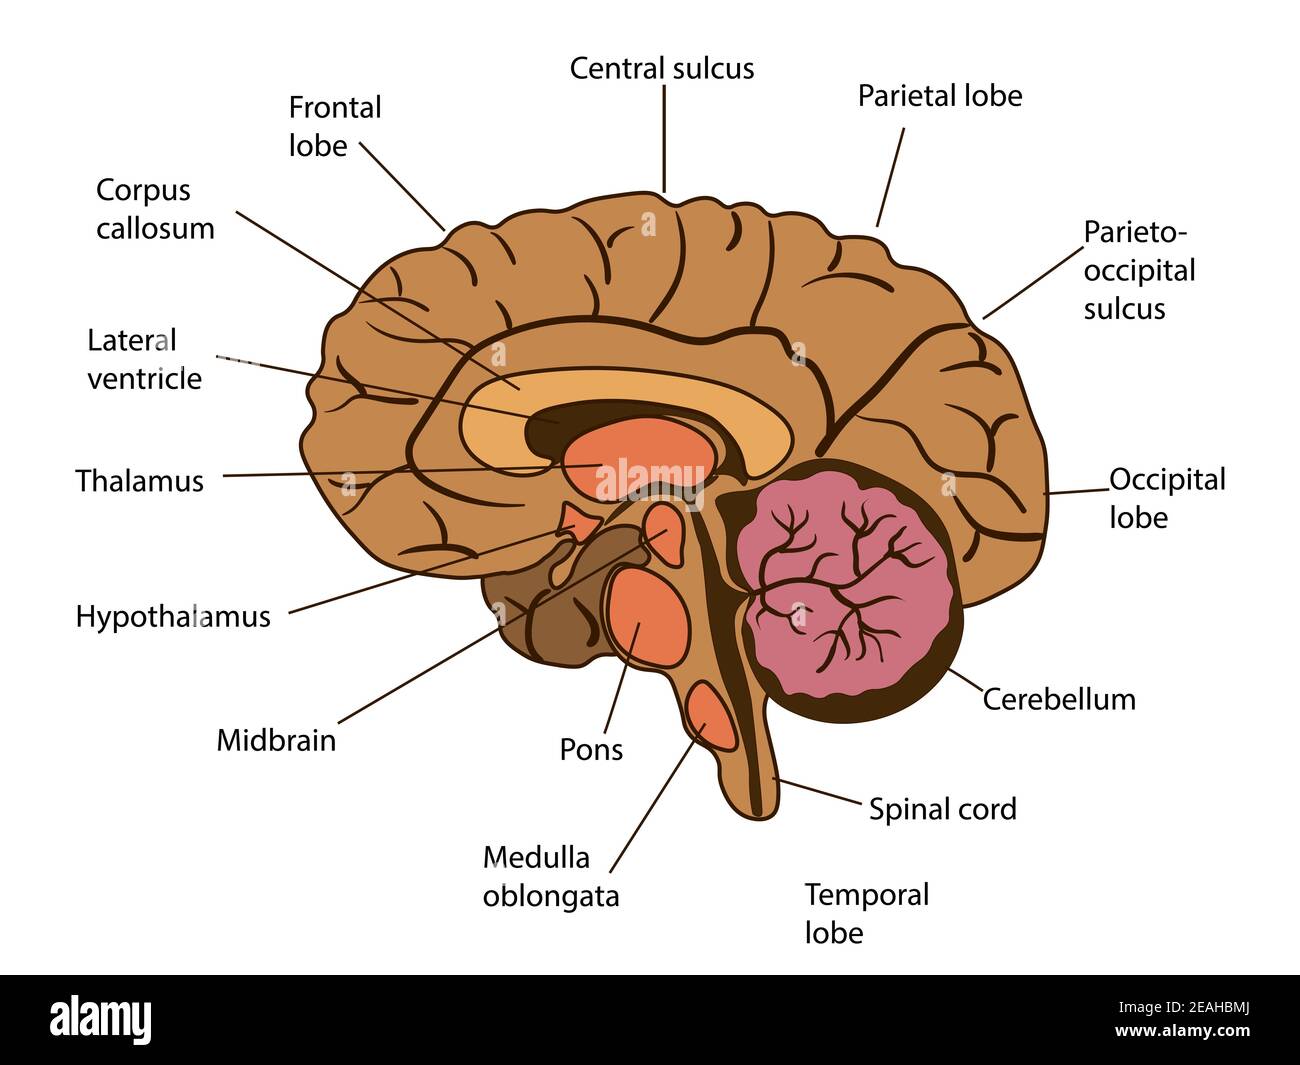

RF2Y8XEWG–Anatomia del cervello umano. Emisferi cerebrali, corteccia cerebrale, frontale, parietale, temporale, lobi occipitali, cervelletto e tronco cerebrale, fessura cerebrale.

RF3BJ1K42–Anatomia del cervello umano. Lobi frontali, occipitali, parietali e temporali, cervelletto e tronco cerebrale. Poster dettagliato del vettore

RF2EAHBMJ–Illustrazione isolata vettoriale dei componenti cerebrali nella testa dell'uomo. Anatomia dettagliata del cervello umano.